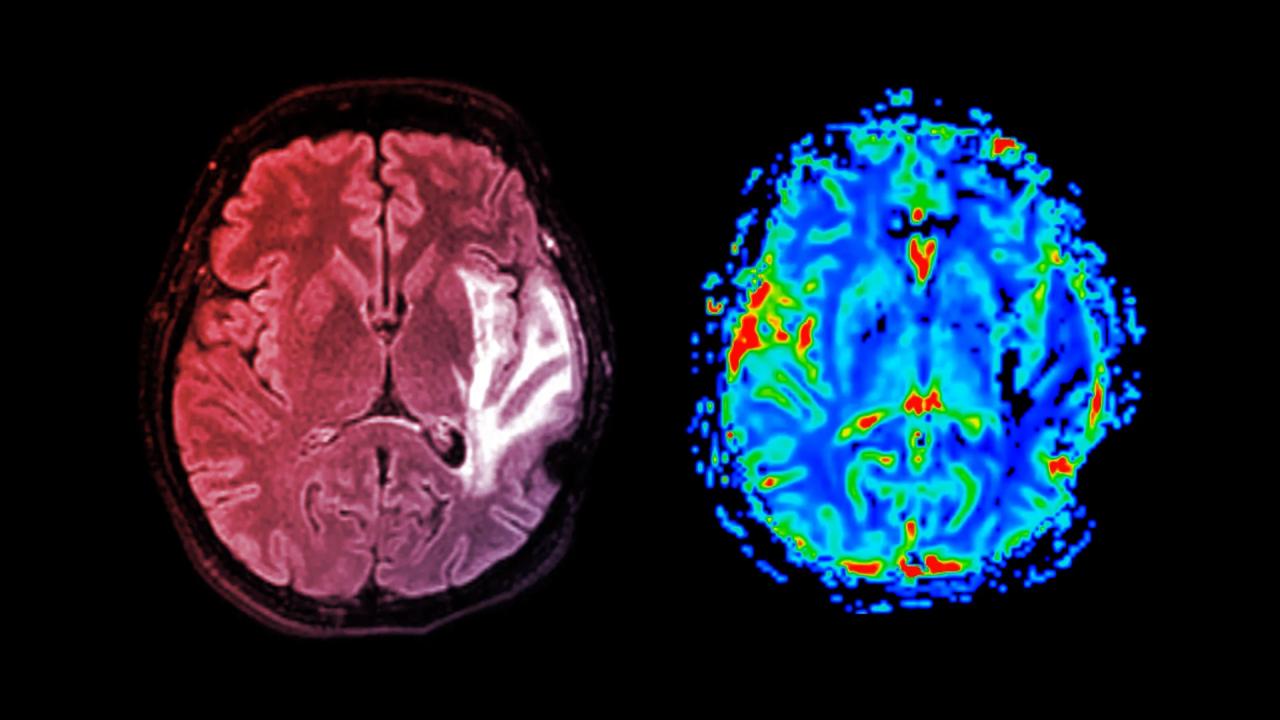

Demencia: lassú romlás, érintett agyterületek

A demencia nem egyetlen betegséget jelent, hanem agyi rendellenességek csoportját fedi. Leggyakoribb formái az Alzheimer-kór, az érrendszeri (vaszkuláris) demencia, illetve a kevert típusú demencia. Mindegyik esetében fokozatosan károsodnak az agysejtek, ez eleinte a memóriát, a gondolkodást és a problémamegoldást érinti, végül viszont beszédzavarhoz, viselkedésváltozásokhoz vezet.

Adataik alapján a demenciához vezető egyik legfontosabb útvonal az érrendszeri károsodás. Bár a túlsúly közvetlenül is növeli a kockázatot, a demencia veszélyének nagy részéért a túlsúllyal együtt járó magas vérnyomás felel. Más szóval, ha sikerül megelőzni vagy kezelni mind az elhízást, mind a hipertóniát, azzal jelentősen csökkenhet a demencia kialakulásának esélye.